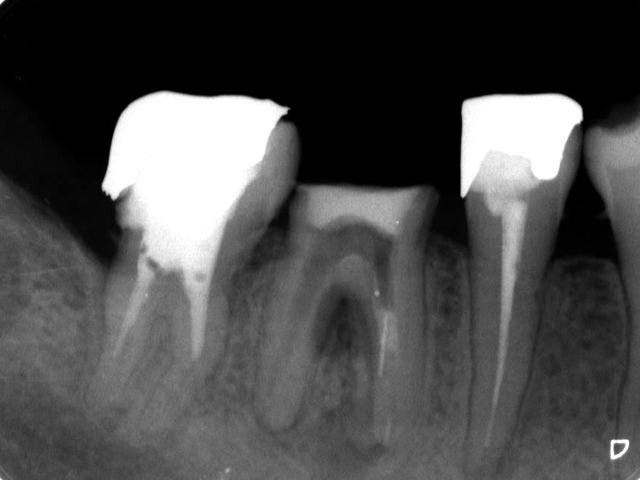

< 症例1 >

- 歯周再生療法

歯周病で破壊、吸収された歯周組織は、その原因を除去することで再生しようとしますが、歯周病に罹患した部分を清掃した後に何もせずそのまま治癒を待つと必要な支持組織が再生する前に歯肉がそこに入り込み歯周組織の再生を阻んでしまいます。GTR法では、歯周ポケット内部を清掃した後にメンブレンと呼ばれる膜を設置し、外から歯肉が入り込まないよう防御することで、メンブレンの下には歯周組織が再生を開始し、ゆっくりと成長していきます。この成長には時間を要しますので、メンブレンの下が新しい組織で満たされるまで一定期間保持しておく必要があります。

GTR法は、歯肉が入り込むのを膜を用いて阻止しますが、エムドゲイン法では、エムドゲイン・ゲルという薬剤を欠損部に注入し、歯周組織の再生を促すとともに、歯肉が入り込むことを防止します。このエムドゲイン・ゲルは時間の経過とともに歯周組織の再生を促しながら吸収していくので、GTR法のように後からもう一度手術を行う必要はありません。